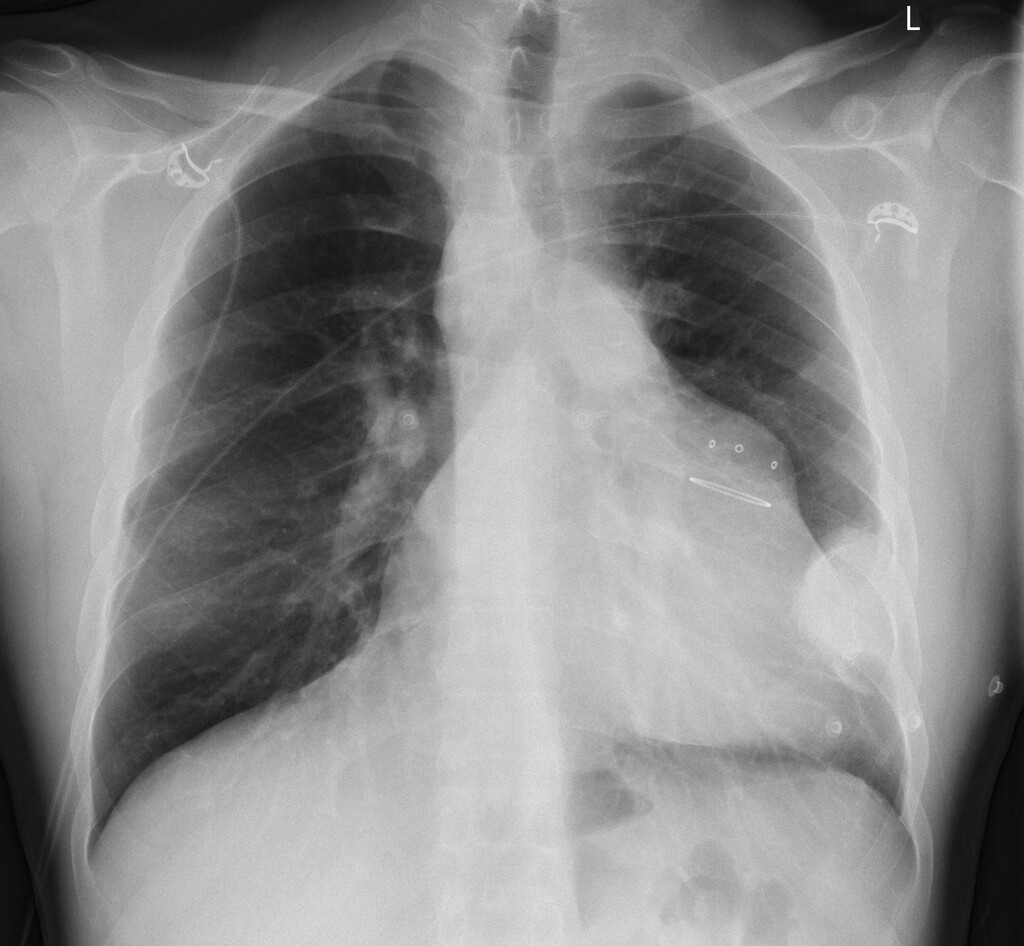

Röntgenbeeld van de borstkas

Deze patiënt heeft sinds drie dagen drukkende pijn links op de borst. Op 3-jarige leeftijd onderging hij een correctie van tetralogie van Fallot en twee jaar geleden een pulmonalisklepvervanging. Nu zijn er geen aanwijzingen voor cardiale afwijkingen bij lichamelijk onderzoek en op het ecg.